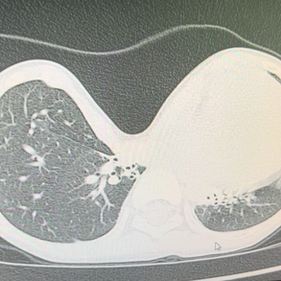

The patient's anterior chest wall exhibits a severe depression, with the deepest part of the depression extending beyond the anterior edge of the spine and sinking into one side of the chest cavity. The heart is severely compressed and completely displaced to the left chest cavity. The Haller index is negative, indicating the most severe type of pectus excavatum.